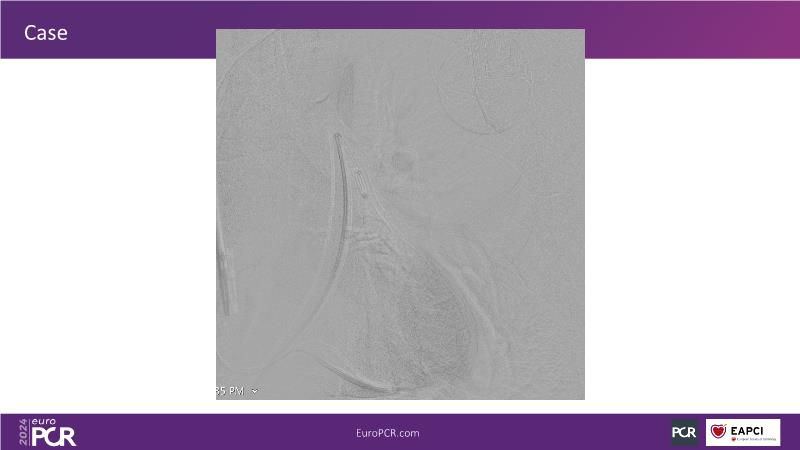

Advancing percutaneous treatment of pulmonary embolism with computer-assisted vacuum thrombectomy

Join this session to delve into innovations in computer-assisted vacuum thrombectomy for acute pulmonary embolism, leveraging real-life case scenarios to share practical experiences and discuss treatment strategies. Amidst the current surge in scientific research, ongoing trials like STORM PE and STRIKE PE are pivotal in shaping the landscape of pulmonary embolism management.